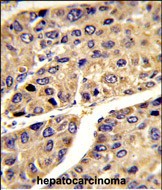

- Formalin-fixed and paraffin-embedded human hepatocarcinoma reacted with IGFALS Antibody (Center), which was peroxidase-conjugated to the secondary antibody, followed by DAB staining. This data demonstrates the use of this antibody for immunohistochemistry; clinical relevance has not been evaluated.